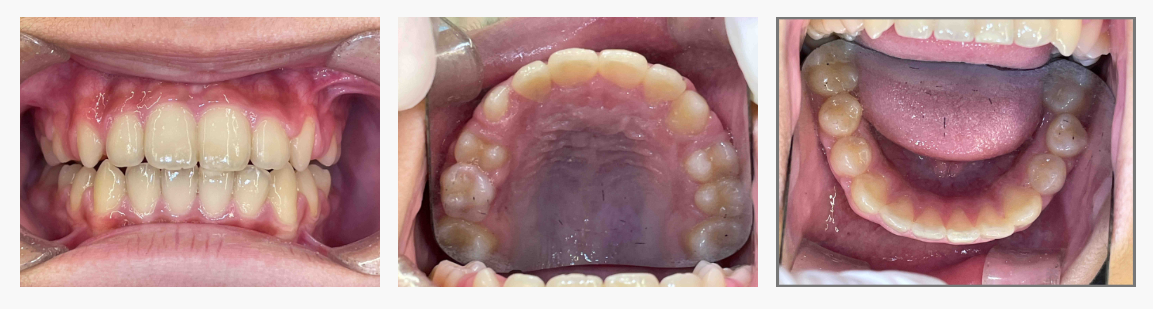

▼ After(治療後)

■ 治療の結果

成長期を活かした治療により、

・上の前歯の突出感が軽減

・口元のバランスが改善

・噛み合わせが安定しやすい状態

となりました。

歯を強制的に動かさず、成長と機能を整えることで得られた結果です。